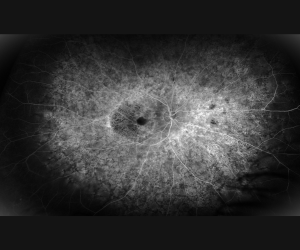

Kelly Zibawa, COA, OS-C, OCT-C, CPT

• Honorable Mention – Monochromatic Category

prph2_od

IRD patient with retinal dystrophy due to PRPH2 variant, OD

prph2_os

IRD patient with retinal dystrophy due to PRPH2 variant, OS